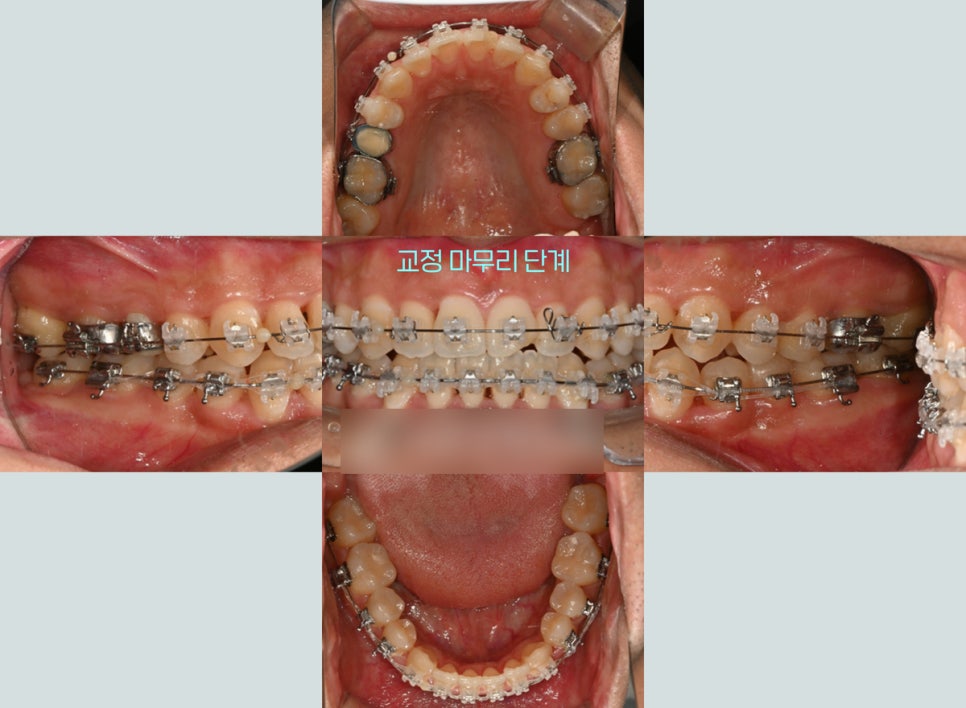

1년 반이 넘어가자 교정을

마무리해도 되겠다는 판단이 들어

세밀한 교합이나 배열을 다시 한번

꼼꼼히 점검하는 시간을 가졌습니다.

이후 장치 제거까지 도와드릴 수 있었는데요.